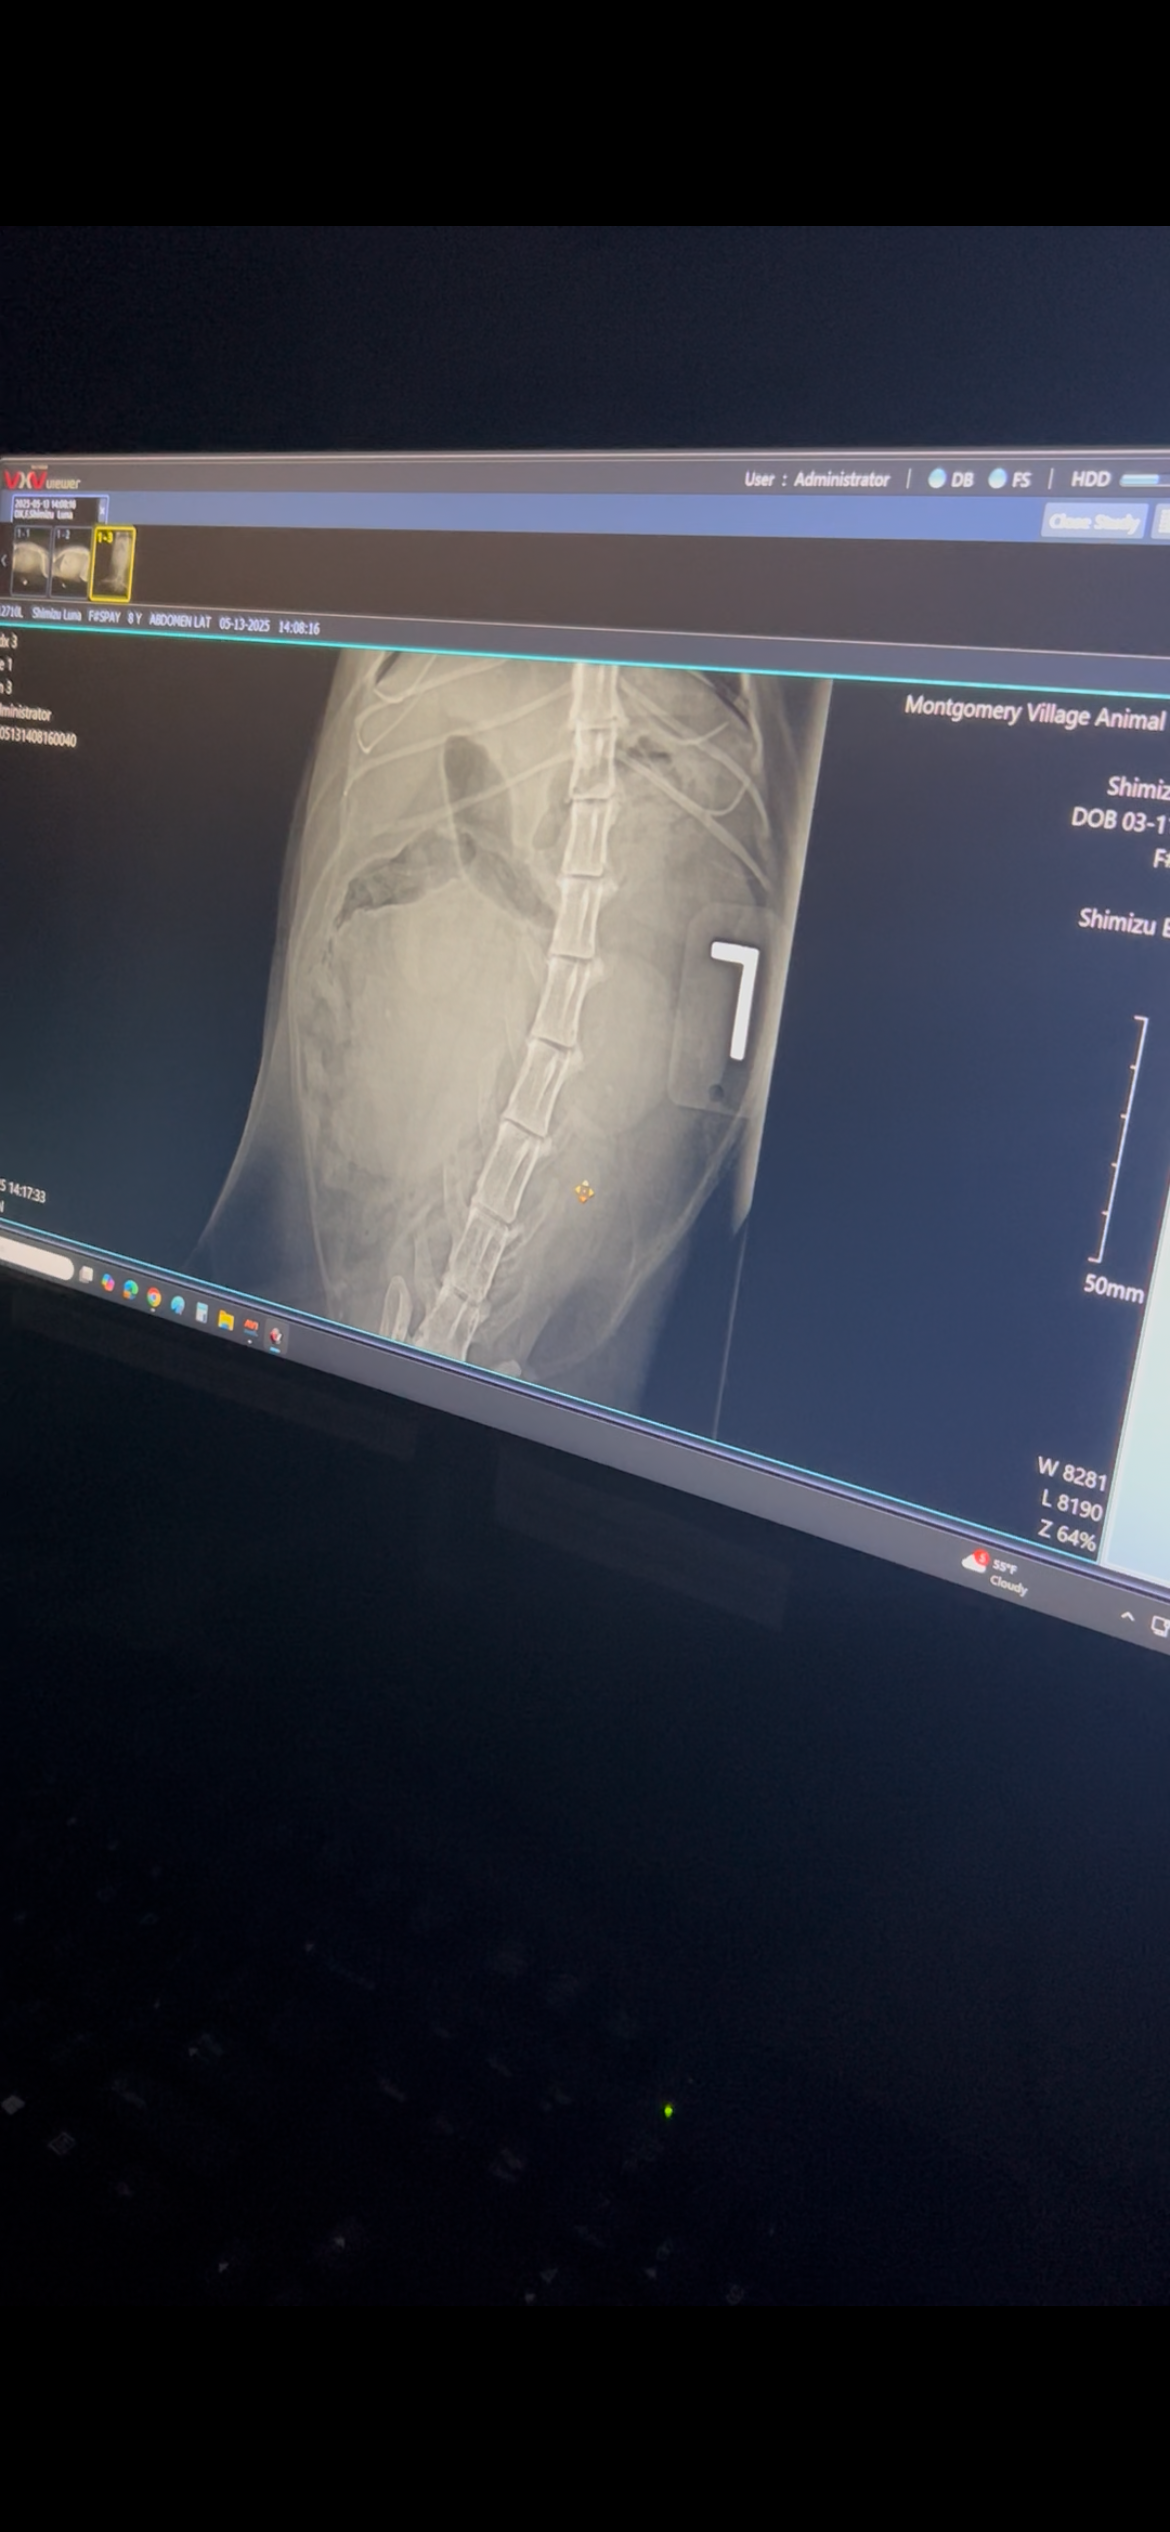

Recently, Luna was found to have a large tumor that requires surgery. Watching her change has been heartbreaking. She went from being her usual cuddly, sweet self to withdrawing and isolating. Luna has always been so expressive, known for using her little voice to “talk” to me throughout the day, but now she barely makes a sound.